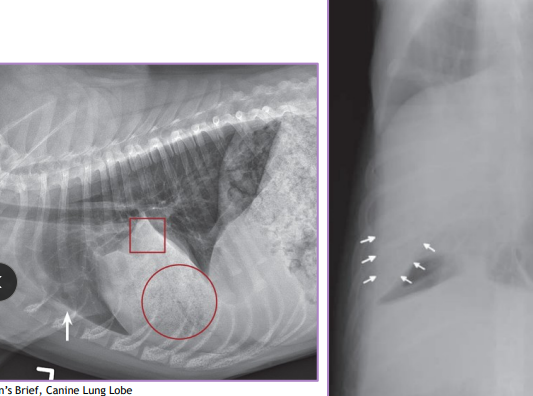

Lung Lobe Torsion

Et: chronic resp dx, chylothorax, trauma, thoracic Sx, neoplasia, idiopathic

Sig: deep, narrow chest dogs - pugs

Cs: right cranial & middle congestion & consolidation - most common

Tx: complete lobectomy

DO NOT untwist lobe